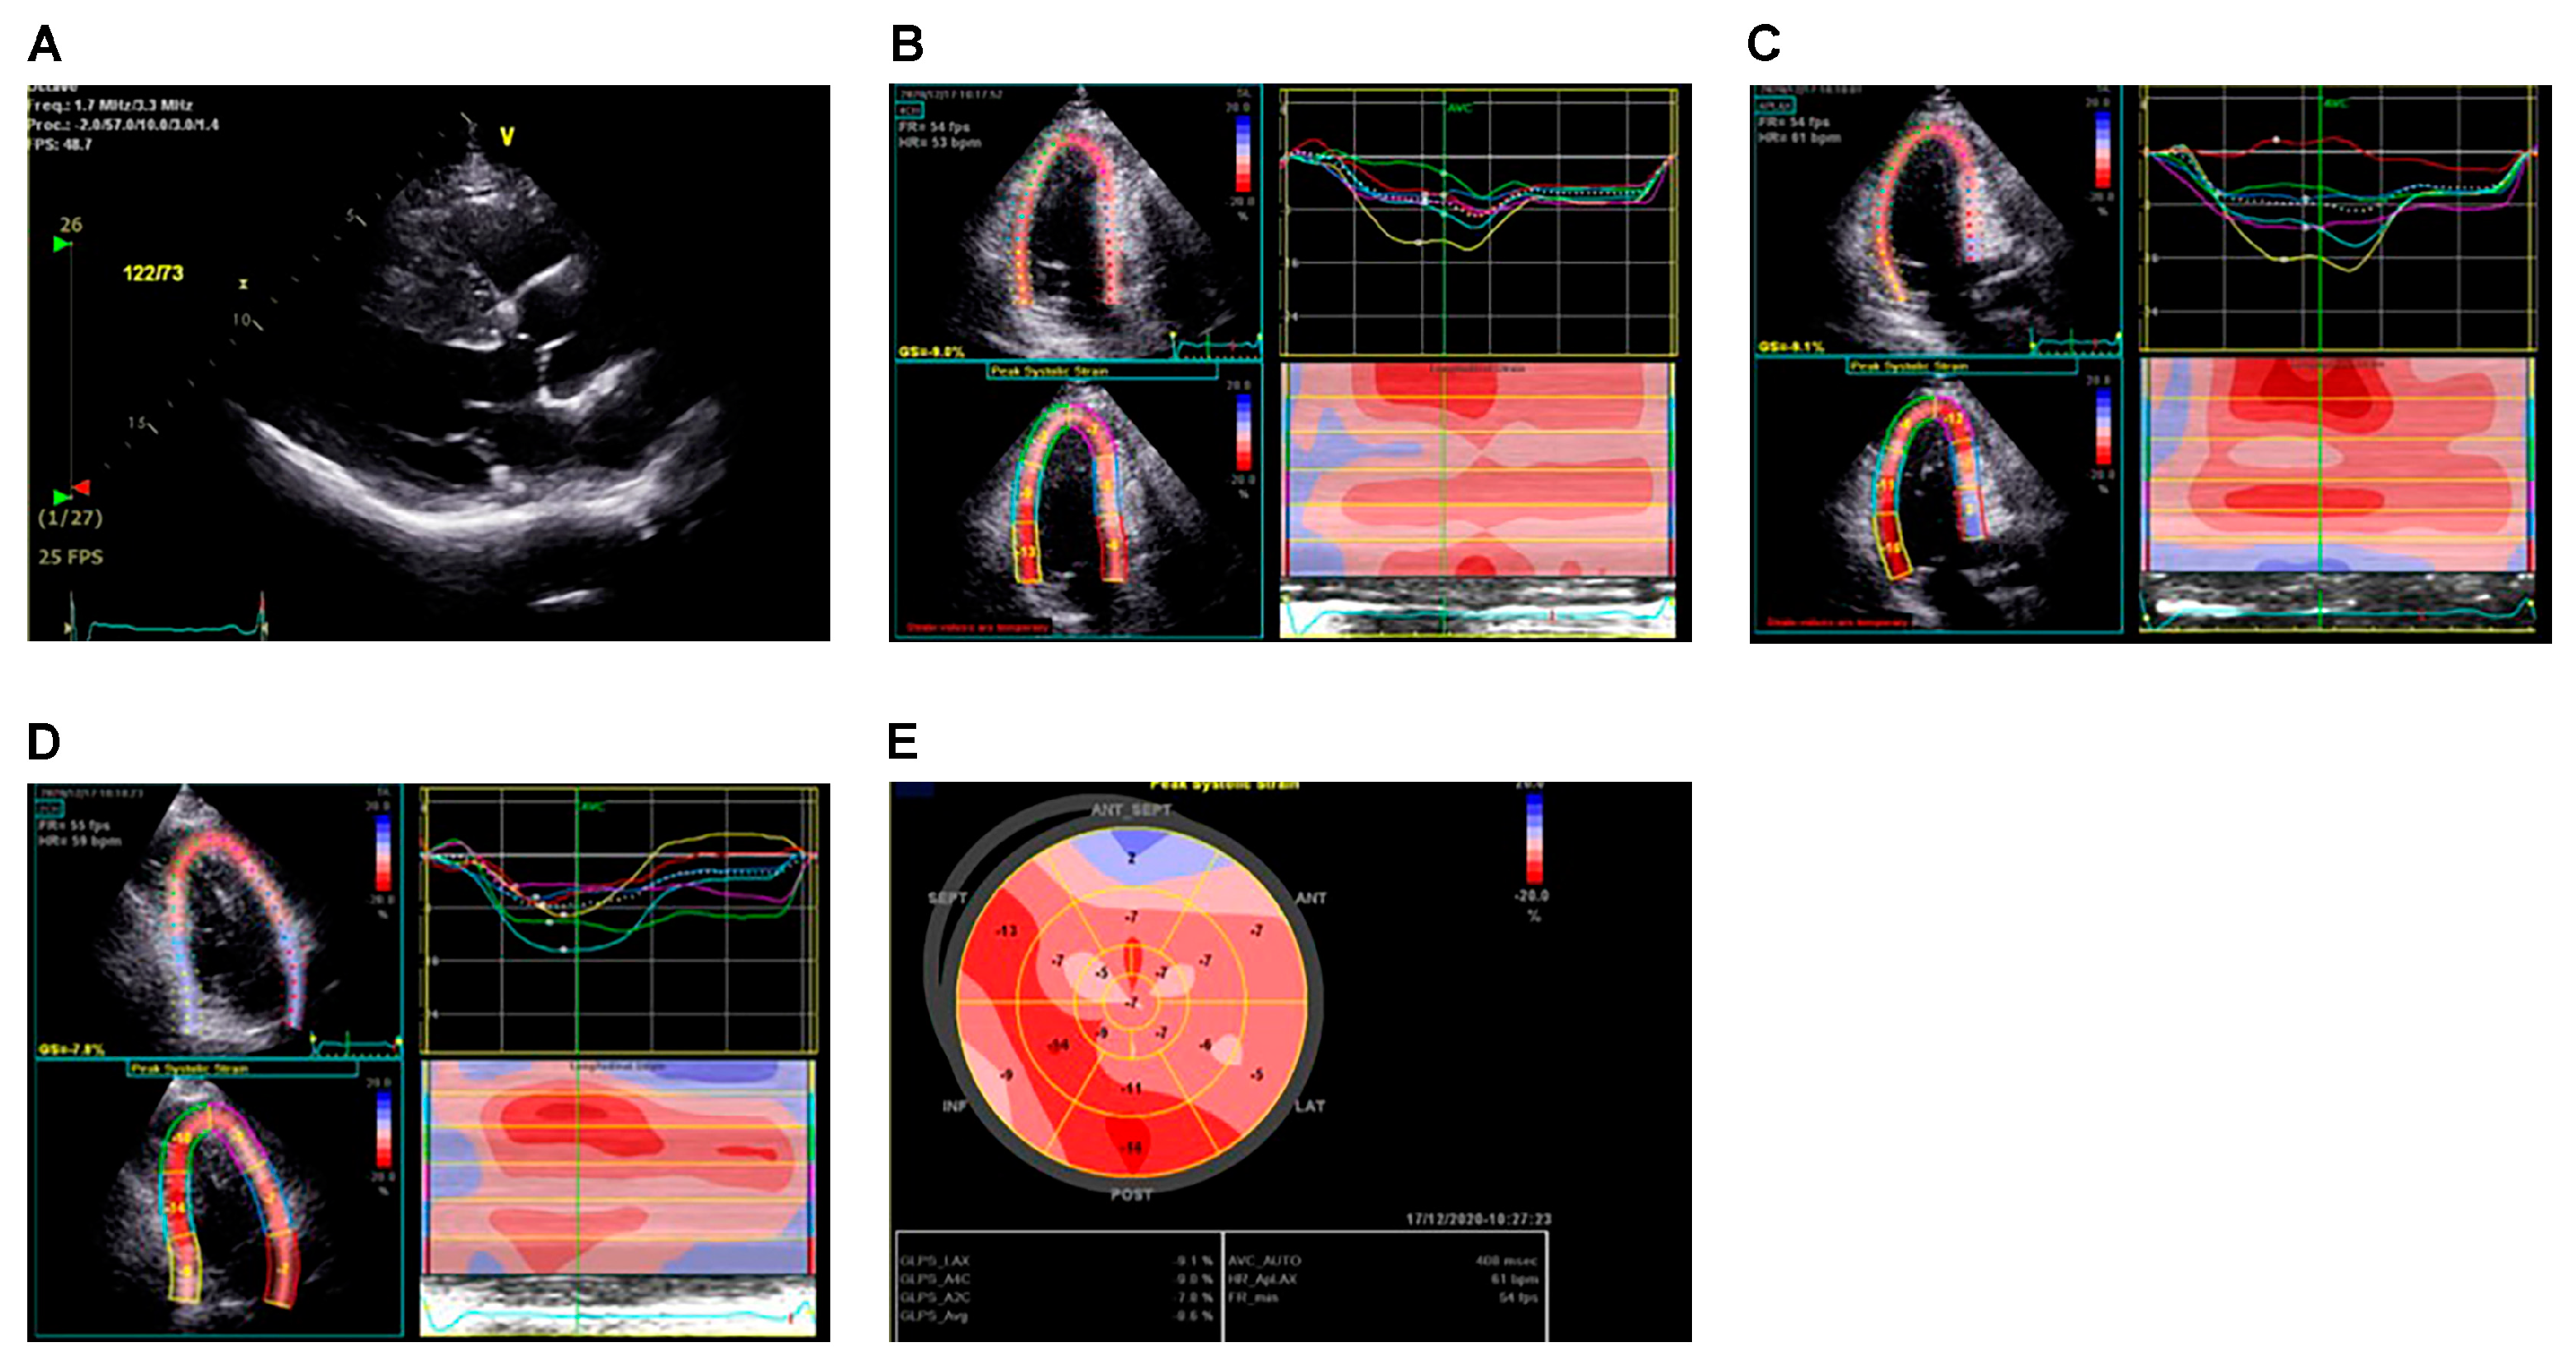

- Carasso, S.; Yang, H.; Woo, A.; Vannan, M.A.; Jamorski, M.; Wigle, E.D.; Rakowski, H. Systolic myocardial mechanics in hypertrophic cardiomyopathy: Novel concepts and implications for clinical status. J. Am. Soc. Echocardiogr. 2008, 21, 675–683. [Google Scholar] [CrossRef]

- Urtado, S.; Hergault, H.; Binsse, S.; Aidan, V.; Ouadahi, M.; Szymanski, C.; Mallet, S.; Hauguel-Moreau, M.; Carlier, R.Y.; Dubourg, O.; et al. Usefulness of Longitudinal Strain Adjusted to Regional Thickness in Hypertrophic Cardiomyopathy. J. Clin. Med. 2022, 11, 2089. [Google Scholar] [CrossRef] [PubMed]

- Kramer, C.M.; DiMarco, J.P.; Kolm, P.; Ho, C.Y.; Desai, M.Y.; Kwong, R.Y.; Dolman, S.F.; Desvigne-Nickens, P.; Geller, N.; Kim, D.-Y.; et al. Predictors of Major Atrial Fibrillation Endpoints in the National Heart, Lung, and Blood Institute HCMR. JACC Clin. Electrophysiol. 2021, 7, 1376–1386. [Google Scholar] [CrossRef] [PubMed]